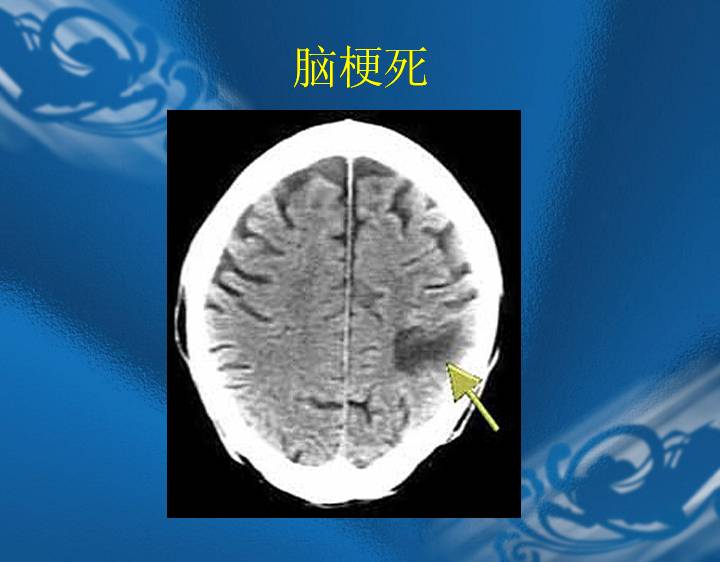

执业医师资格考试“实践技能”影像学辅导资料